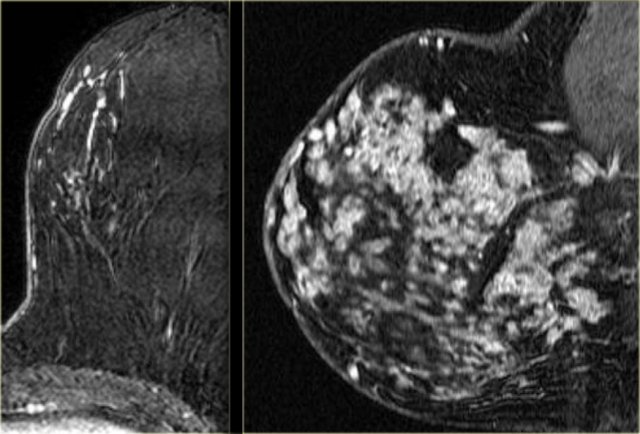

Clumped enhancement

Clumped enhancement is the most important non-mass enhancing pattern to recognize.

It has a 60% chance of cancer (typically DCIS).

On the left two examples of clumped enhancement in DCIS.